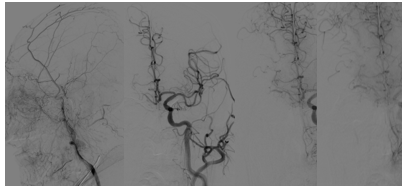

结论:DWI高信号,患者无明显症状(额颞梗死),前交通动脉开放,右侧大脑中动脉显影,考虑右侧颈内动脉慢性闭塞,不除外急性闭塞及急性血栓栓塞。患者于入院后约11小时左右再次出现左侧肢体无力症状,给予静脉替罗非班8ml推注,6ml/小时持续泵入,30分钟症状无缓解。

• 急诊造影发现右侧颈内慢性闭塞,颈内起始部位光滑,基本不见残端。颈内动脉末端有显影,右侧大脑中动脉不显影,考虑病因是右侧颈内动脉慢性闭塞导致血流淤滞进而形成血栓,致使大脑中动脉闭塞。

• 先疏通右侧颈内,放置Carotid Wallstent支架后,输送中间导管和Guiding取大脑中血栓,术后替罗非班持续泵入。